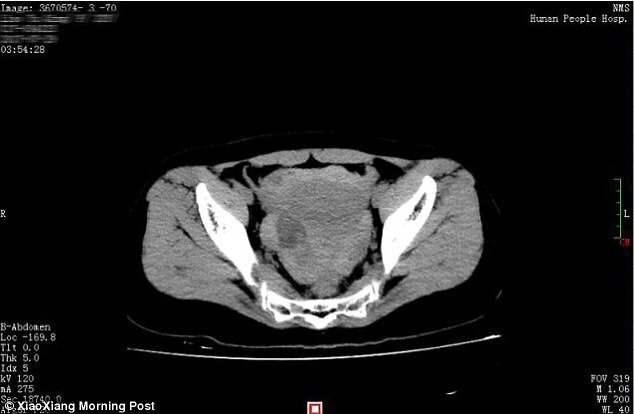

Một cặp đôi ở Trung Quốc do "yêu" quá nồng nhiệt đã làm người vợ bị vỡ nang buồng trứng, gây xuất huyết nghiêm trọng, phải nhập viện cấp cứu trong tình trạng nguy kịch.